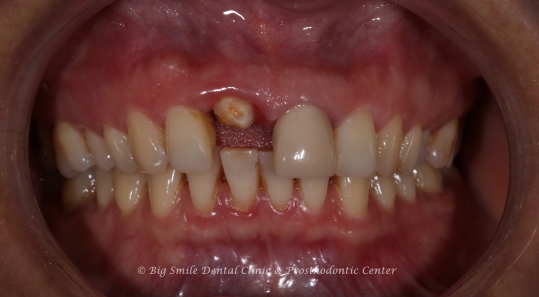

Figure: Surgical Guide

On the day of the guided implant procedure at our clinic in Kathmandu, Nepal:

The surgery was minimally invasive and painless, and the patient remained comfortable throughout.